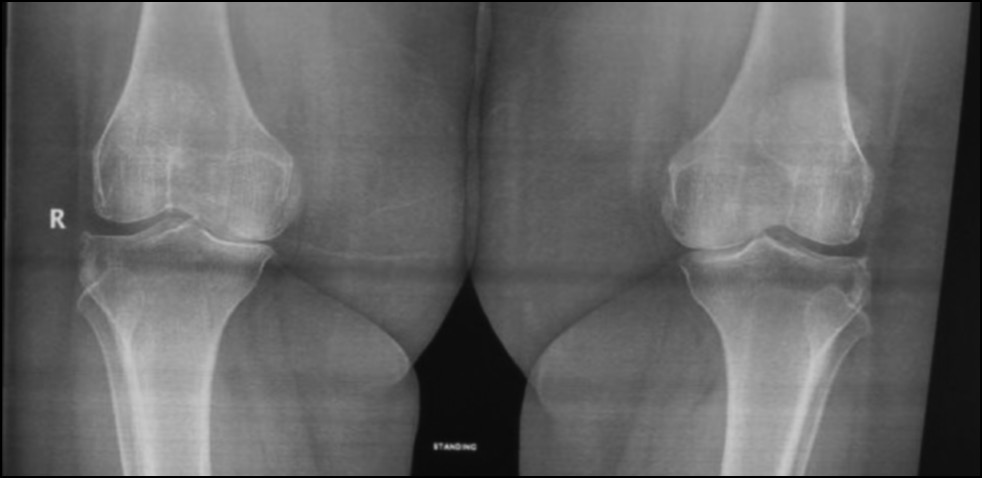

Fig. 19. Ap preoperative x-ray showing bilateral knee osteoarthritis.

Рис. 19. Предоперационная рентгенограмма с двусторонним остеоартритом коленного сустава.

CASE 3. PATIENT 24

Age: 60 years.

Sex: Female.

Diagnosis: Bilateral advanced knee osteoarthritis.

Procedure: Bilateral simultaneous knee arthroplasty.

Associated illnesses: DM and hypertension.

Postoperative follow-up: No postoperative complications were encountered.

Length of hospital stay: 6 days.

Radiological assessment (Fig. 19–22)